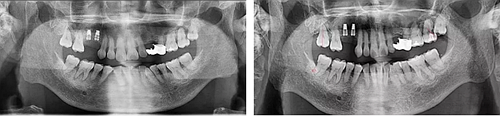

術(shù)后當(dāng)天 術(shù)后7個月

術(shù)后8個月 術(shù)后10個月

術(shù)后13個月

術(shù)后14個月